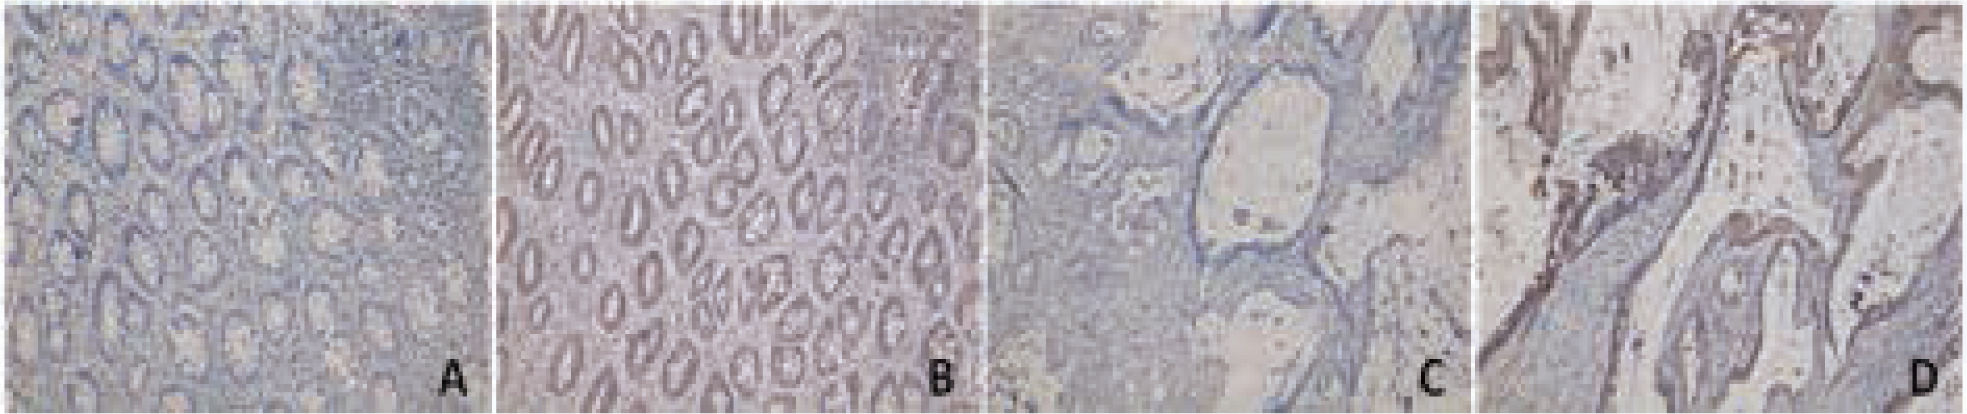

In this study, galectin-3 was primarily expressed in the cytoplasm and cell membrane with yellow-brown granules. The positive rates of galectin-3 in cancer tissues and adjacent normal tissues were 62.5% (38/61) and 13.0% (3/23), respectively. Galectin-3 positive expression rate was significantly higher in cancer tissues than that in adjacent normal tissues (P<0.05), Figure 1.

Galectin-3 expression in colorectal cancer tissue and normal intestinal tissues by immunohistochemistry

(A: galectin-3 negative expression in normal intestinal tissues, × 200; B: galectin-3 positive expression in normal intestinal tissues, × 200; C: galectin-3 negative expression in colorectal cancer tissues, × 400; D: galectin-3 positive expression in colorectal cancer tissues, × 400)